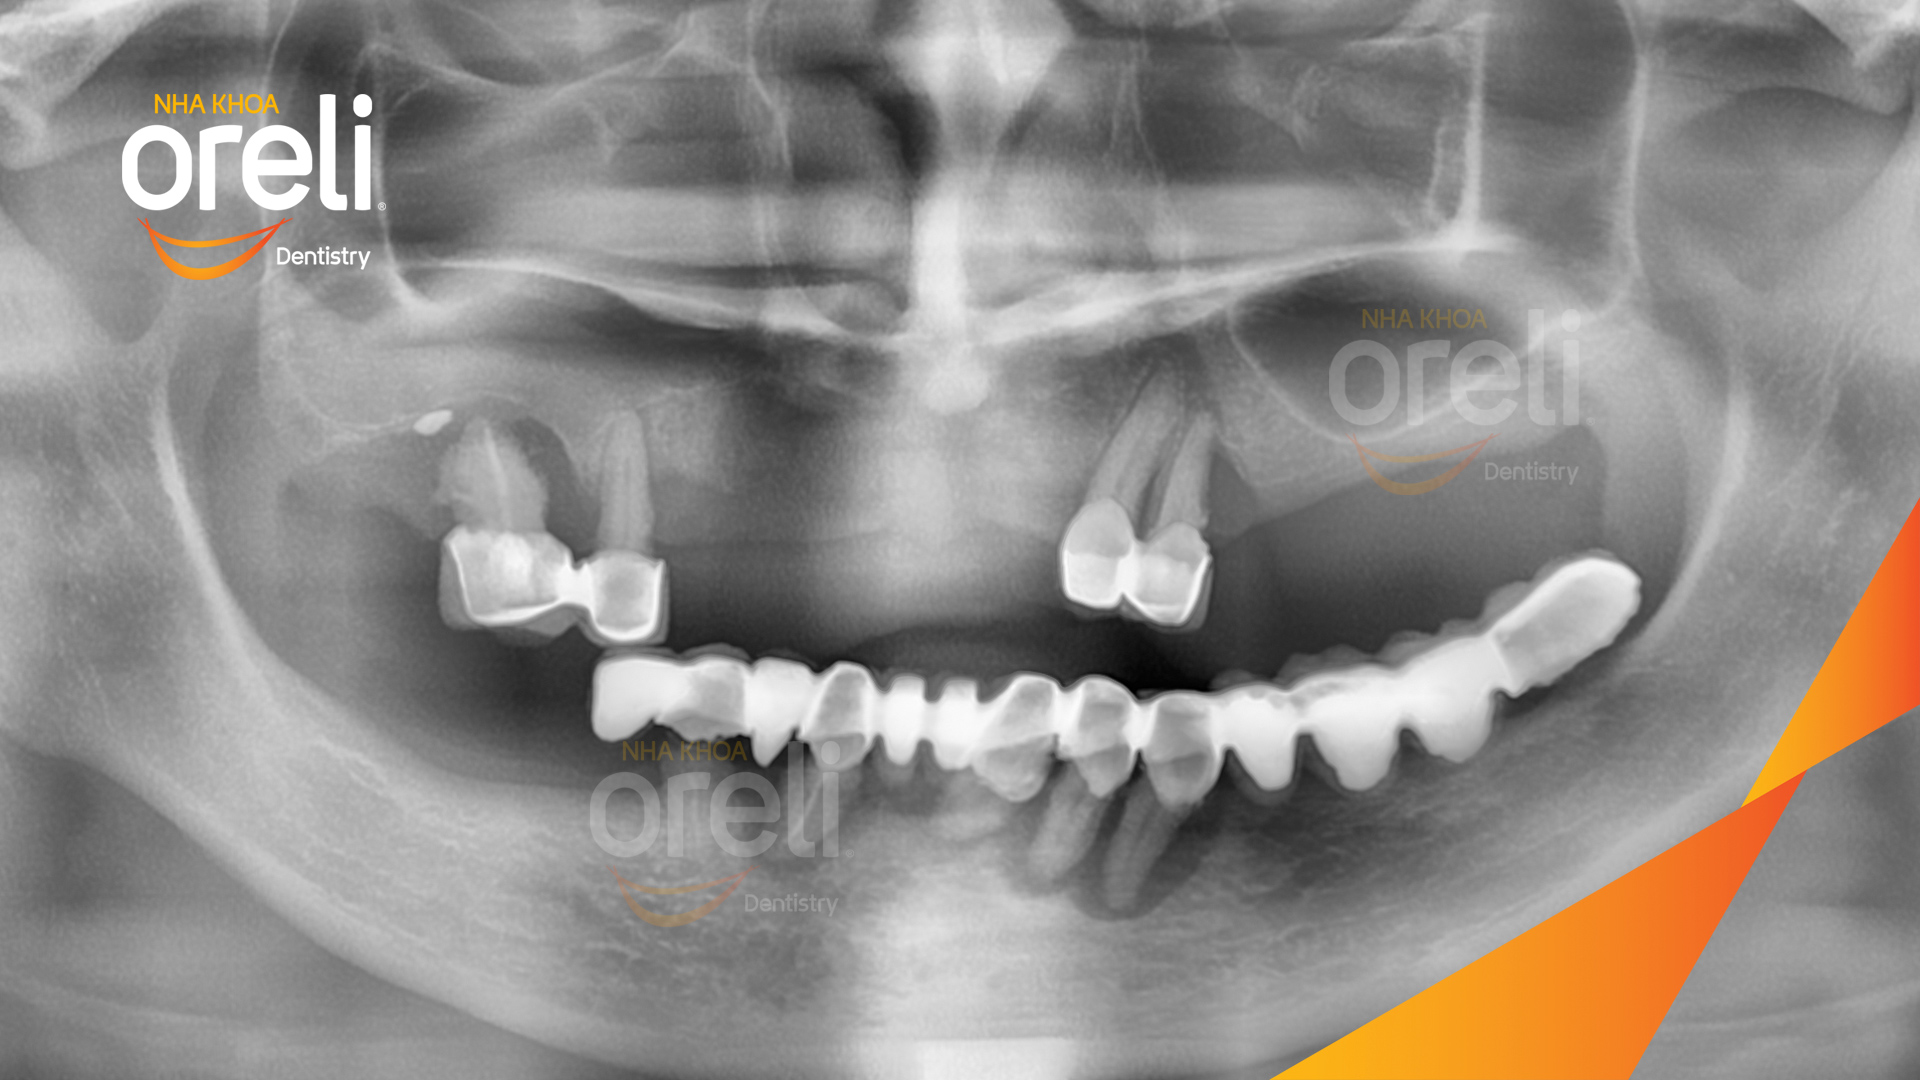

Tình trạng: Cầu răng sứ lâu ngày, tiêu xương nhiều ở cả hàm trên và dưới

Hình ảnh thực tế